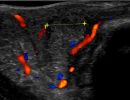

Πολλές αλλοιώσεις και παθήσεις μπορούν να απεικονιστούν υπερηχογραφικά και να μελετηθούν αξιόπιστα με τη βοήθεια του Έγχρωμου Doppler και της Ελαστογραφίας .

- Αιμαγγειώματα, αγγειοδυσπλασίες (αγγειακού τύπου βλάβες)